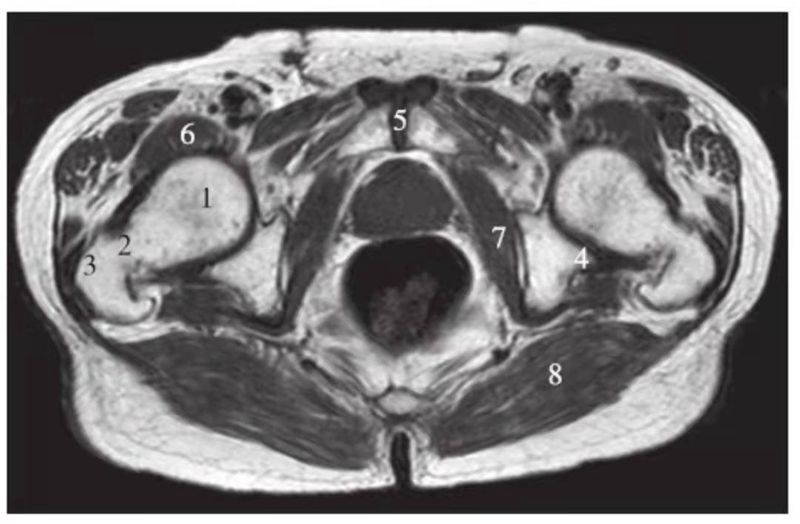

正常髋关节经股骨头内缘层面T1WI像

1.髂骨;2.臀大肌;3.圆韧带;4.股骨头;5.坐骨;6.闭孔外肌;7.耻骨肌;8.大收肌